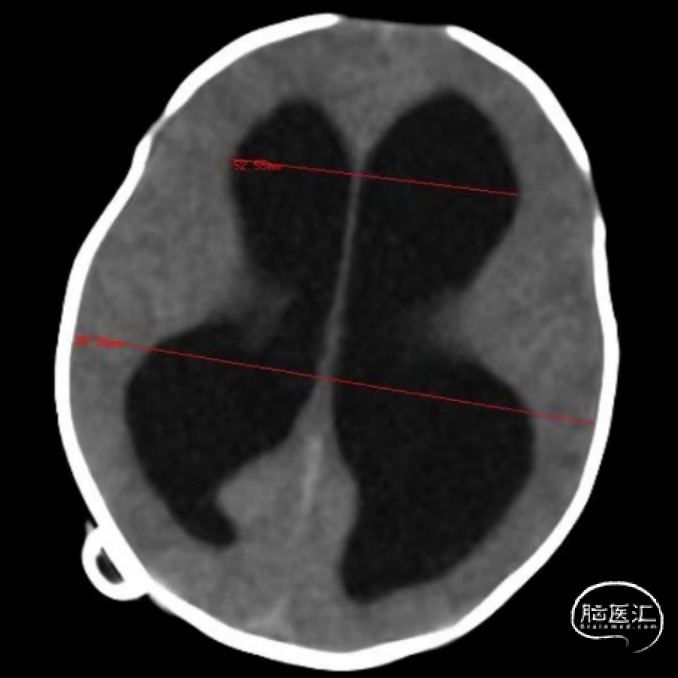

术前CT

Evans index(EI)≈0.55

重度脑积水,透明隔腔明显增宽,双侧脑室、三脑室、脚间池明显扩张、积水,周围脑实质受压,左侧大脑半球脑梗死。